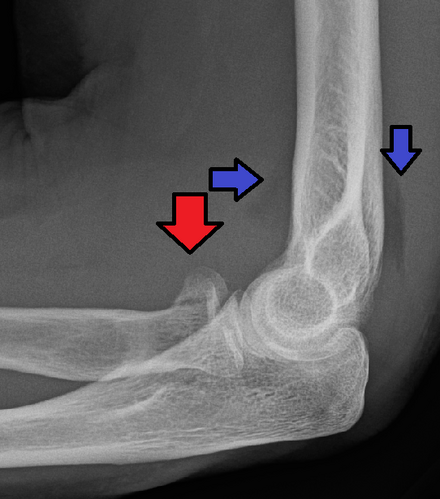

This X-ray taken from the side shows an olecranon fracture in which the pieces of bone have moved out of place (displaced).

Reproduced from Konda SR: Fractures around the elbow, in Egol KA, Gardner MJ, eds: Let’s Discuss Management of Common Fractures. Rosemont, IL, American Academy of Orthopaedic Surgeons, 2016, pp. 17-30.